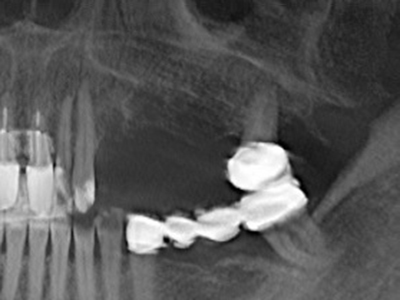

Aplicación: Preparación cerca del nervio

Si es preciso realizar intervenciones quirúrgicas en las que el hueso está en contacto directo con estructuras sensibles, como son los vasos sanguíneos o los nervios, los instrumentos rotativos presentan un enorme potencial de provocar lesiones iatrogénicas. Así, precisamente en la representación de nervios después de una lesión iatrogénica, o en el transcurso de la lateralización de un nervio para resecciones, reconstrucciones o incorporación de implantes, los equipos piezoeléctricos pueden resultar muy útiles para preparar la tapa ósea y retirar las partes de tejido duro cercanas al nervio (fig. 17-20). Por lo general, un ligero contacto del cordón nervioso con el inserto piezoeléctrico no tiene consecuencia alguna; ahora bien, un procedimiento poco cuidadoso con movimientos tipo sierra o piezas de trabajo sobre la base ósea aún existente puede provocar lesiones nerviosas temporales o incluso permanentes. Con todo, el riesgo de sufrir una lesión de este tipo se considera significativamente inferior que en los casos en los que se utilizan sierras y fresas (Pereira, Gealh et al. 2014).